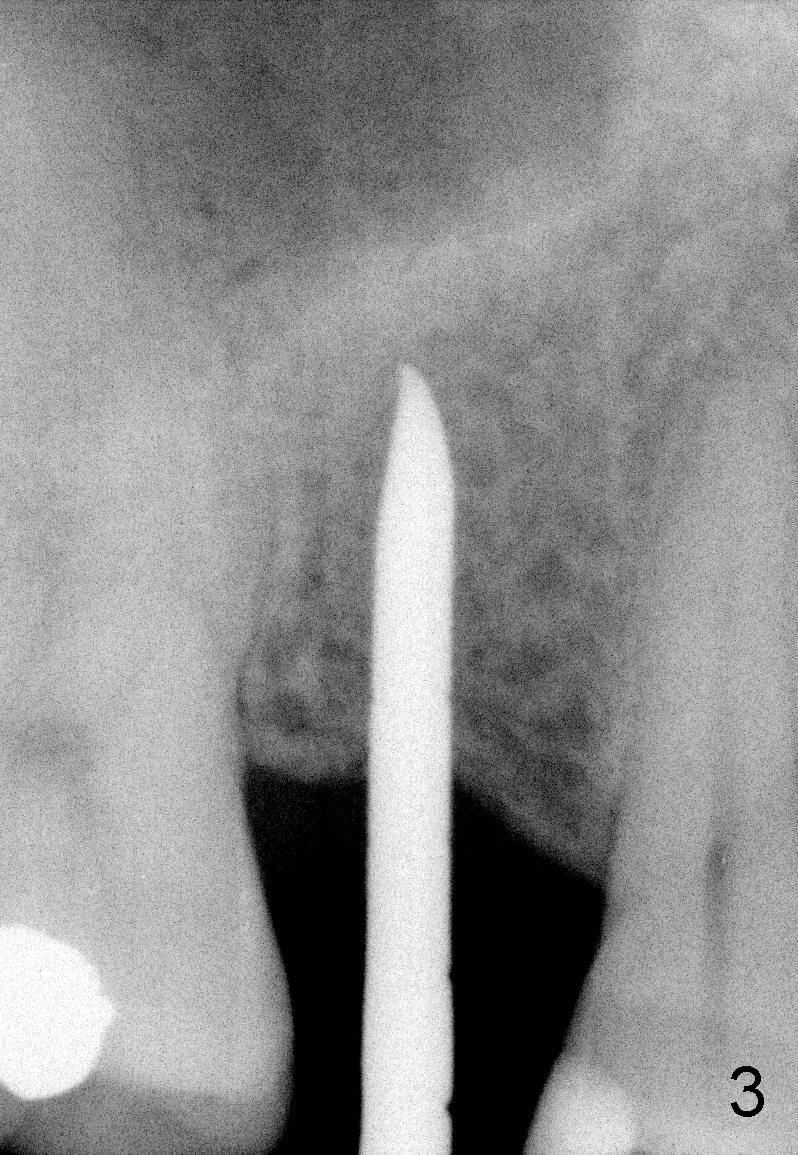

The tooth #4 was removed from a 41-year-old man (Fig.1). Fig.2 was taken 1 year and 7 months post extraction. Osteotomes (Fig.3,4) were used to create osteotomy (7 yr 9 m post ext). A 4x14 mm implant was placed below the sinus floor with insertion torque > 60 Ncm (Fig.5). The surgery was flapless (Fig.6). No antibiotic was taken pre- and post-op. The implant was found to be tender and loose. It was removed without bone graft.